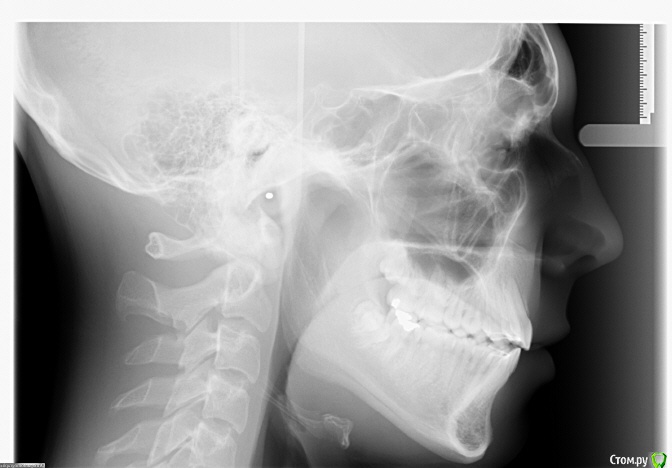

LeoRuss Опубликовано 7 января, 2016 Поделиться Опубликовано 7 января, 2016 Пациенту 17, три месяца назад сняли брекеты которые носили чуть больше года, поставили ретейнеры.Текущий контрольный осмотр у ортодантиста занял пять минут, но..на основе панорамника предписано удалять все восьмерки.Внимательно просмотрев множество уже существующих здесь постов на сюжет удаления ретинированных и дистопированных зубов мудрости, осознал почему их лучше стоит удалить (особенно лежачую 48ку), увидел почему это лучше сделать раньше, пока не отросли закривульные корни, и не дожидаться «а вдруг», но решился все же создать новую тему и задать свой насущный вопрос:А можно ли не ждать, но попытаться их как то сохранить, а еще лучше и поправить расположение этих, еще не выпуклившихся, но уже сформировавшихся рудиментов??Наверняка же были уже пациенты, врачи, времена когда этот вопрос всесторонне отпрепарировали? Пошлите меня пожалста куданить где можно получить данную информацию, желательно позитивную. И конечно буду признателен за ваши личные ПМСМ по конкретной ситуации, снимки прилагаю. Ссылка на комментарий

Doc Опубликовано 7 января, 2016 Поделиться Опубликовано 7 января, 2016 Пациенту 17, три месяца назад сняли брекеты которые носили чуть больше года, поставили ретейнеры.Текущий контрольный осмотр у ортодантиста занял пять минут, но..на основе панорамника предписано удалять все восьмерки.Внимательно просмотрев множество уже существующих здесь постов на сюжет удаления ретинированных и дистопированных зубов мудрости, осознал почему их лучше стоит удалить (особенно лежачую 48ку), увидел почему это лучше сделать раньше, пока не отросли закривульные корни, и не дожидаться «а вдруг», но решился все же создать новую тему и задать свой насущный вопрос:А можно ли не ждать, но попытаться их как то сохранить, а еще лучше и поправить расположение этих, еще не выпуклившихся, но уже сформировавшихся рудиментов??Наверняка же были уже пациенты, врачи, времена когда этот вопрос всесторонне отпрепарировали? Пошлите меня пожалста куданить где можно получить данную информацию, желательно позитивную. И конечно буду признателен за ваши личные ПМСМ по конкретной ситуации, снимки прилагаю. V Panoramique_05-01-2016.JPGV Profil_05-01-2016.JPGТак сохранить-то как раз не проблема. В Вашем случае даже есть шанс, что они вырастут и встанут на место, но при этом они так подвинут весь зубной ряд, что вся красота может скучиться и все, за что боролись не один год, пойдет прахом. Оно Вам надо? Ссылка на комментарий

колесников Опубликовано 7 января, 2016 Поделиться Опубликовано 7 января, 2016 Вовсе они не лежащие. Удалятся легко. Сейчас самое время. Ссылка на комментарий

diesel87 Опубликовано 7 января, 2016 Поделиться Опубликовано 7 января, 2016 Верхняя левая точно уже никуда сама не выйдет, нижние скорее всего упрутся в семерки и как верно сказал doc, нарушат всю красоту. Ссылка на комментарий